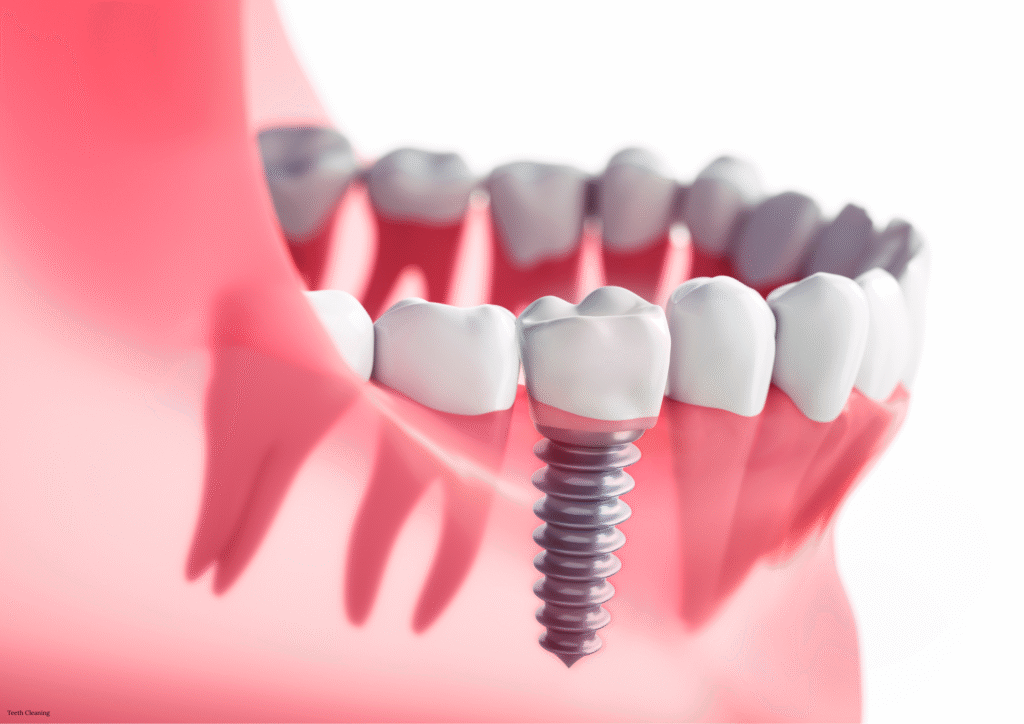

Implants Placed

0

+